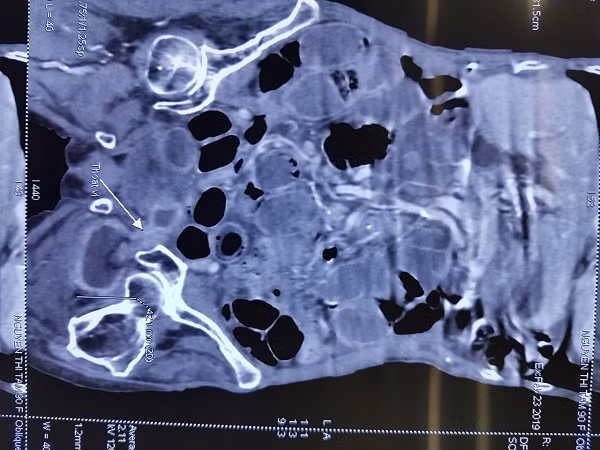

Hình ảnh chụp CT của bệnh nhân cho thấy thành ruột bị hoại tử, nhiều lỗ thủng

Qua thăm khám và chụp cắt lớp vi tính ổ bụng, bệnh nhân được chẩn đoán là tắc ruột do thoát vị bịt nghẹt bên trái ngày thứ 12, nghi đã có hoạt tử ruột gây áp xe hố bịt, nguy cơ phải cắt đoạn ruột. Vì thế, bệnh nhân được chỉ định mổ cấp cứu.

Quá trình mổ, sau khi giải phóng quai ruột nghẹt ra khỏi lỗ bịt, các bác sĩ thấy thành ruột của bệnh nhân đã bị hoại tử lỗ thủng đường kính 2cm, bờ mép nham mở mủn nát, đồng thời có dịch mủ chảy từ trong hố bịt trái.